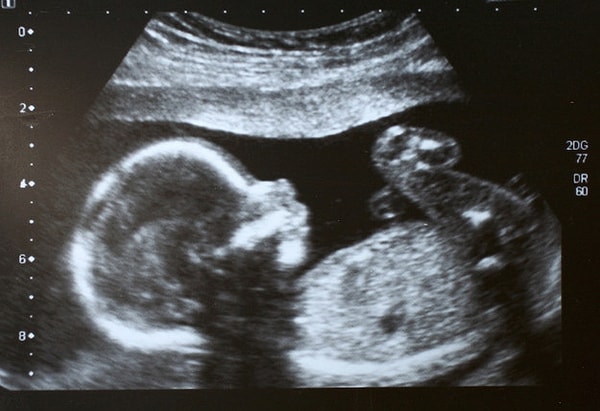

17. Этап развития лица малыша.